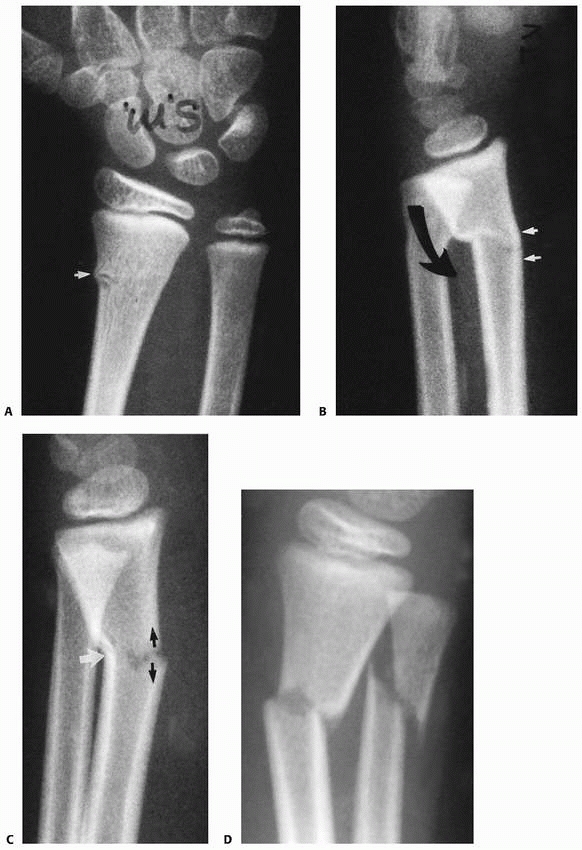

|

FIGURE 9-31 A,B. A 10-year-old boy sustained a closed Salter-Harris type I separation of the distal ulnar physis (arrows) combined with a fracture of the distal radial metaphysis. C. An excellent closed reduction was achieved atraumatically. D. Long-term growth arrest of the distal ulna occurred.